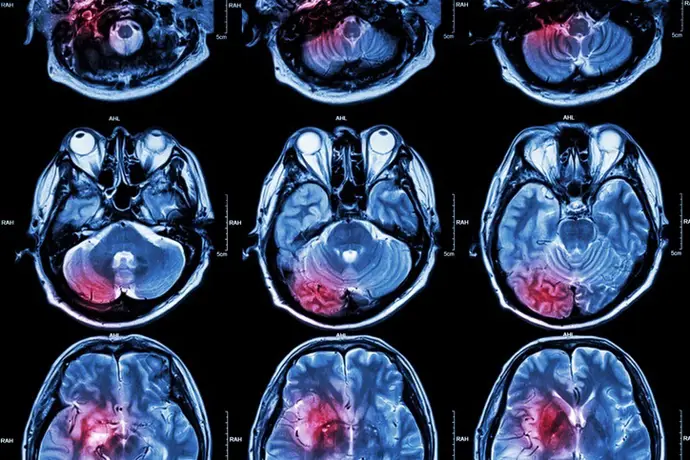

MADRID, 23 de enero (EUROPA PRESS) – Un equipo de científicos de la Universidad McMaster, ubicada en Canadá, ha descubierto una nueva forma de retardar el crecimiento del glioblastoma, que es la forma más agresiva y actualmente incurable de cáncer cerebral. Además, han identificado un medicamento existente que podría utilizarse para tratar esta enfermedad.

La investigación fue publicada en la revista ‘Neuron’ y liderada por científicos de la Universidad McMaster y el Hospital para Niños Enfermos (SickKids) de Canadá. El estudio demuestra que ciertas células cerebrales, que anteriormente se creía que solo apoyaban la función nerviosa saludable, en realidad contribuyen al crecimiento y propagación del glioblastoma.

Se sabe que el glioblastoma crece formando una red de células que se comunican y se apoyan mutuamente, y la interrupción de estas conexiones puede ralentizar el desarrollo del cáncer. Este estudio profundizó en qué neuronas están implicadas. Los investigadores hallaron que un tipo de célula llamada oligodendrocito, habitualmente responsable de proteger las fibras nerviosas, puede intercambiar funciones y, en efecto, favorecer el crecimiento tumoral.